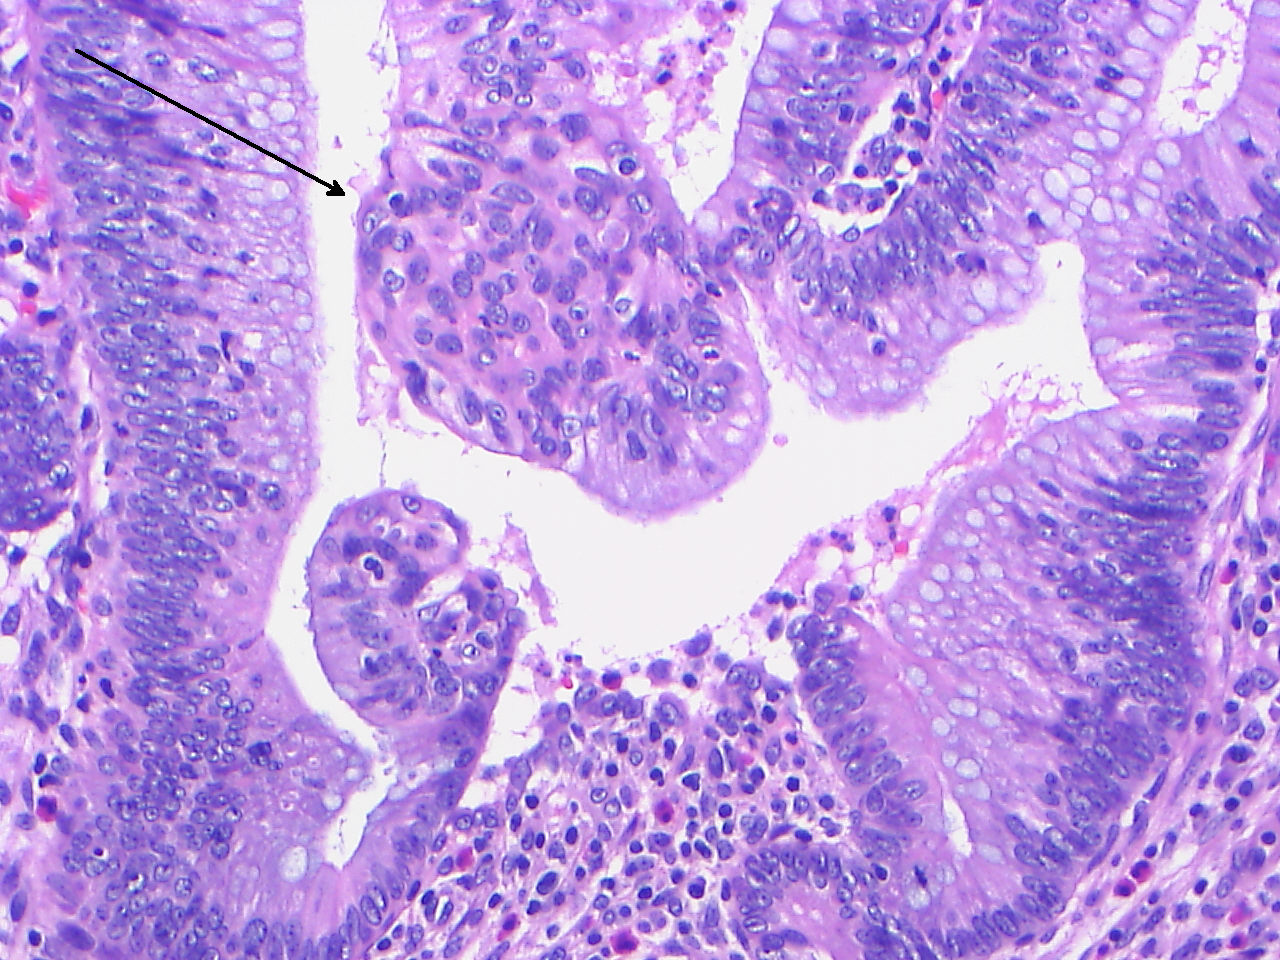

Фотографии медицинских исследований инсулиномы и синдрома Триады Уиппла